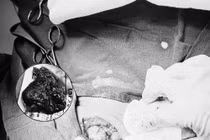

Vừa qua, các bác sĩ tại Trung tâm Y tế Quảng Yên đã thực hiện ca bóc tách u nang cổ nghi rò khe mang – một loại dị tật bẩm sinh hiếm gặp, thường không được nhận biết cho đến khi gây biến chứng.